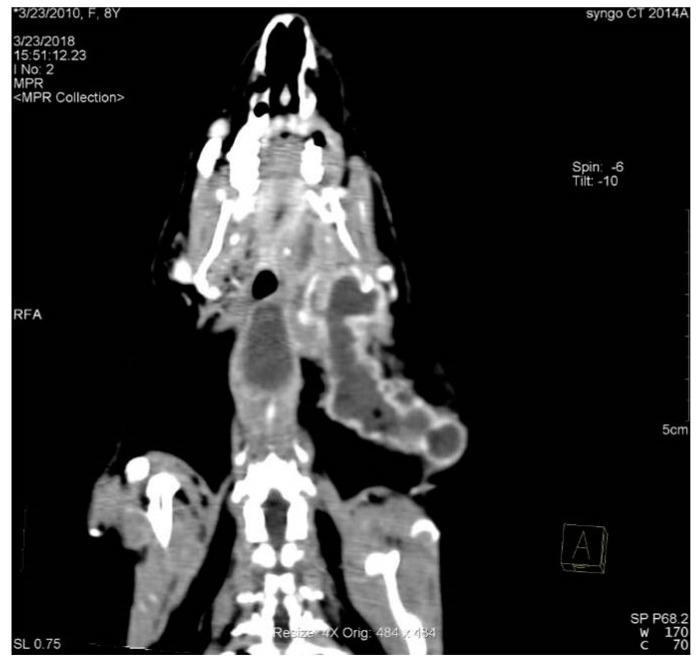

Domestic rabbits have teeth that grow throughout the animal's life and are prone to disease. Clinical signs of dental disease in domestic rabbits are non-specific, and, therefore, a definitive diagnosis usually requires additional methods. This study was carried out on a group of 105 domestic rabbits aged 3 to 9 years. In total, 90 domestic rabbits with dental disease visible on CT images and other secondary diseases of the head area qualified for this study. Malocclusion was found in 57 (63.3%). Retrograde elongation of the tooth apices in the mandible was present in 39 (43.3%), and it was present in the maxilla in 48 (53%). Clinical tooth crowns were overgrown in 39 (43%). Dental abscesses were present in 54 (63%). Secondary to the presence of a dental abscess, osteomyelitis was found in 43 (79% of the animals with a dental abscess). Dental inflammatory resorption was found in 36 (40%). Secondary to dental disease, nasal cavity inflammation was found in 18 (20%). Otitis media was present in six (6.7%). The most common dental disease found in this study's animals was malocclusion secondary to abnormal clinical crown abrasion and abnormal tooth growth. In domestic rabbits, osteomyelitis is a common complication of dental abscesses. Computed tomography is an invaluable diagnostic method in the diagnosis of dental disease and secondary diseases of the head area, such as inflammation of the nasal cavities or otitis media, in pet rabbits.

家兔的牙齿会在其一生中不断生长,且容易患病。家兔牙齿疾病的临床症状不具有特异性,因此,通常需要借助其他方法才能做出明确诊断。本研究针对105只年龄在3至9岁的家兔展开。共有90只家兔符合研究条件,这些家兔在CT图像上可见牙齿疾病以及头部区域的其他继发性疾病。其中,57只(63.3%)存在错牙合。下颌骨牙尖逆行伸长的有39只(43.3%),上颌骨有48只(53%)。临床牙冠过长的有39只(43%)。存在牙脓肿的有54只(63%)。继发于牙脓肿,发现43只患有骨髓炎(占患有牙脓肿动物的79%)。发现牙炎性吸收的有36只(40%)。继发于牙齿疾病,发现18只患有鼻腔炎症(20%)。患有中耳炎的有6只(6.7%)。本研究中家兔最常见的牙齿疾病是继发于临床牙冠异常磨损和牙齿异常生长的错牙合。在家兔中,骨髓炎是牙脓肿的常见并发症。计算机断层扫描在诊断宠物兔的牙齿疾病以及头部区域的继发性疾病(如鼻腔炎症或中耳炎)方面是一种非常有价值的诊断方法。